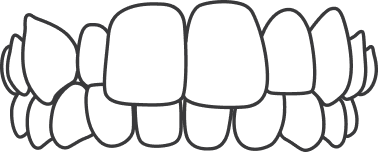

An underbite occurs when the lower teeth protrude past the front teeth, preventing normal function of your front teeth or molars.